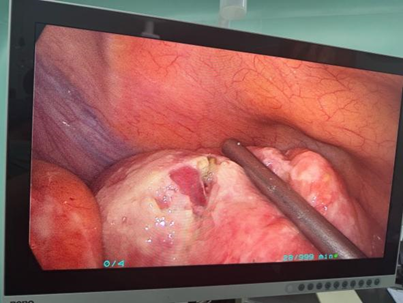

术中发现:乙状结肠多发憩室,长约 20 cm,其中直乙交界处可见一憩室穿孔,穿孔大小约 0.5*0.5 cm,穿孔处可见少量粪水流出。其余憩室壁薄,炎症明显。

结肠及部分小肠壁大量黄色脓苔附着,肠壁及系膜水肿增厚明显。盆腔、左侧结肠旁沟及部分小肠系膜间隙有粪水样液体残留。肝、胆、胃及其余肠管未见明显异常。

黄凯主任将探查情况向家属交代,并指出手术如果行一期吻合,术后吻合口瘘的概率很大,为确保围术期安全,沟通后决定行 全腔镜下乙状结肠部分切除术+乙状结肠造口术。